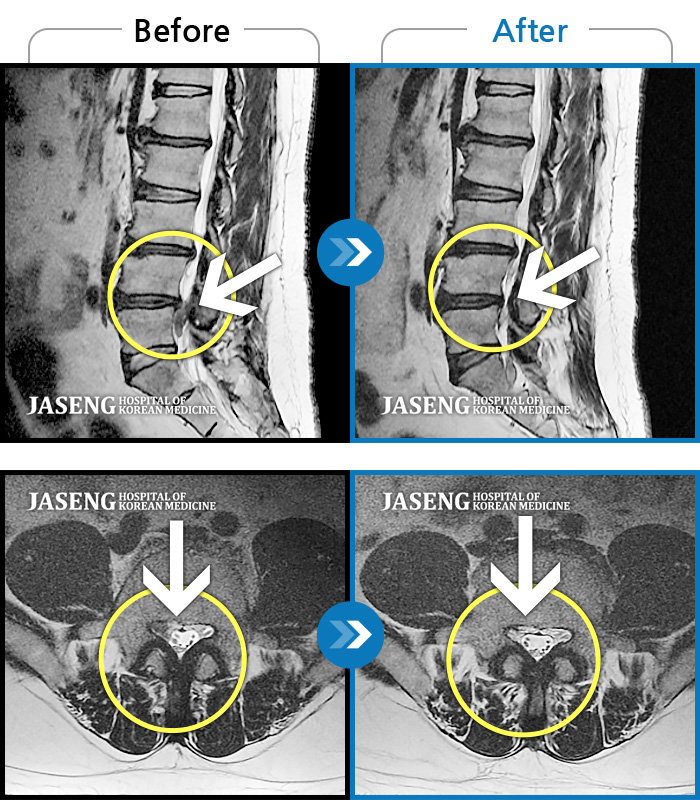

Before

After

환자에게 사전 동의를 받아 동일 조건에서 촬영되었습니다.

개인에 따라 치료 후 부작용이 발생할 수 있으니 의료진과 상담 후 치료를 진행하시기 바랍니다.